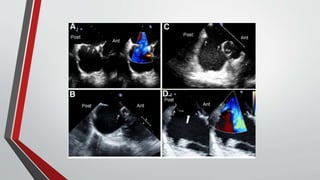

Echocardiography

• The functional importance of the defect can be estimated by the size of the right ventricle,

• The presence or absence of right ventricular volume overload (paradoxical septal motion),

• (less accurately) estimation of Qp/Qs.

• Indirect measurement of pulmonary artery pressure can be obtained from the Doppler velocity of the tricuspid

regurgitation jet.

• In ostium secundum atrial septal defects, : The mitral valve abnormalities consist of thickening and fibrosis of leaflets and

chordae tendineae .

• TEE permits better visualization of the interatrial septum and is usually required when device closure is contemplated,

partly to ensure that pulmonary venous drainage is normal

• ICE can be used instead of TEE during device closure to help guide insertion of the device, thereby reducing fluoroscopic

and procedural time and forgoing the need for general anesthesia.